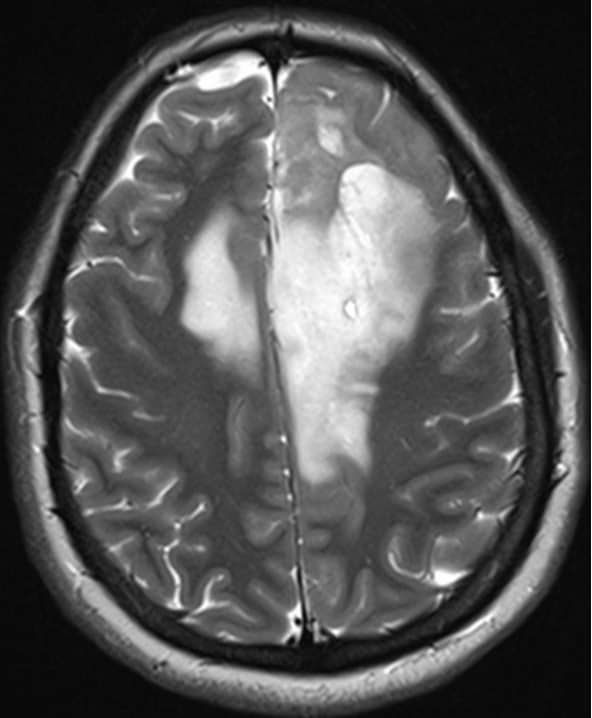

Чуть больше месяца назад в отделение поступила девушка 33 лет с жалобами на периодическую головную боль и однократный эпизод утраты сознания. При МРТ головного мозга выявлена большая опухоль обеих лобных долей с поражением мозолистого тела, размером 11,1х6,5х7,5см. (объем 283,3см3). Основной массив опухоли локализовался в левой лобной доле, подходя вплотную к зонам на коре, отвечающим за движения в правых конечностях и за произношение слов. В глубине опухоль находилась в непосредственной близости от речевых трактов и пирамидных трактов с двух сторон. Повреждение их могло привести к нарушениям речи или парализации пациентки. Мозолистое тело (структура, которая соединяет два полушария мозга между собой) было поражено опухолью на 75%. Разобщение полушарий (пересечение мозолистого тела) может привести к выраженным психическим нарушениям. В структуре опухоли проходили крупные сосуды, питающие до 30% полушарий. Все это делало предстоящую операцию действительно сложной. Так же напрягало еще то, что больную кроме умеренной головной боли ничего больше не беспокоило.

На послеоперационных МРТ видно, что опухоль удалена на 98,3%. Небольшой ее фрагмент в задних отделах пришлось оставить из-за прорастания ей двигательных зон.